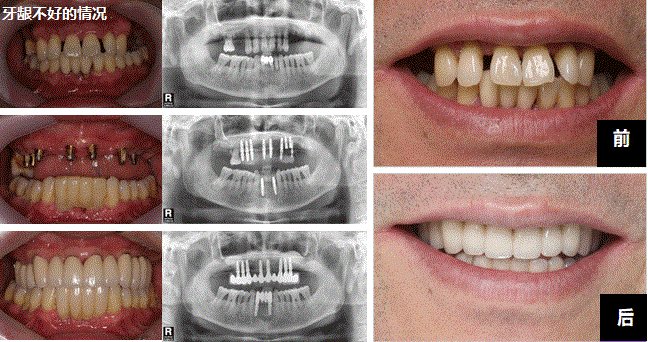

没有牙齿的患者也别担心!我们PARK AVENUE的缺牙种植牙手术是大部分牙齿也没有的人也可以手术种植牙。使用我们的技术秘诀牙龈骨头不足,细细的情况也制作固定性口康假体治疗的缺牙种植牙手术。

牙齿完全没有的时候也使用种植牙可以离开假牙。使用7~12个左右的种植牙制作口康假体,可以跟正常牙齿一样使用。咬的力也比使用假牙的时候强,而且不用带假牙的优点也有。通过PARK AVENUE的技术秘诀细心地考虑牙齿的状态和骨头吸引程度植立正确和安全的种植牙。